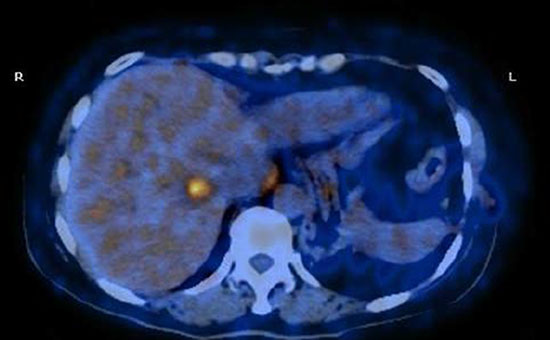

After the surgery, the patient did not undergo any adjuvant therapy due to her refusal. She continued the regular oncological follow-up. Four months later, she complained epigastric discomfort. CEA is still abnormal (CEA 124.2 ng/ml). Fluoro-deoxy-glucose positron emission tomography/computed tomography (FDG-PET/CT) scan confirmed a gastric malignancy (SUV19.4) at the level of the cardias with a paraesophageal lymph node metastasis (SUV11.5) (Figure 3). Subsequently, biopsy through endoscopic ultrasonography (EUS) defined the bulky lesion as a poorly differentiated carcinoma with mucosal ulceration, easy bleeding, located at the fundus, measuring 4*4 cm in diameter. The patient had no history of Helicobacter pylori infection.

Figure 3: PET/CT scan showing the gastric lesion in the cardia.